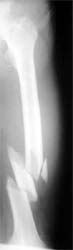

股骨多段粉碎骨折 采用闭合穿钉法,带锁髓内钉内固定